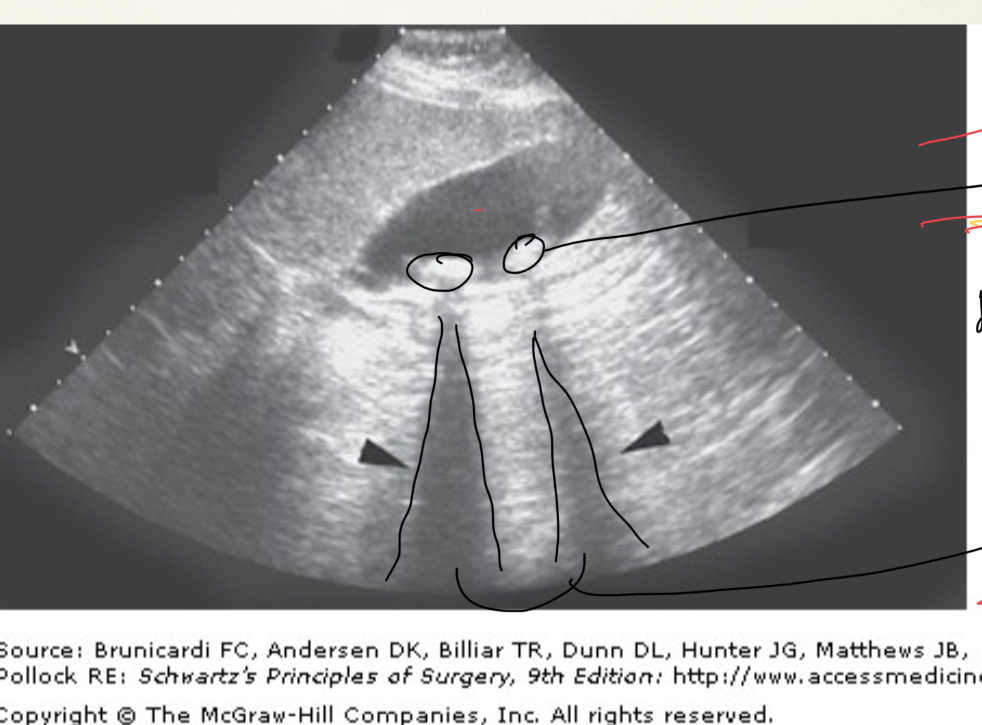

¿Que observamos en 1,2 y 3?

A

1.- conducto hepático común

2.- colédoco

3.- 2da porción del duodeno

¿Qué son las sombras hiper-ecogénicas?

son las sombras que proyectan las piedras